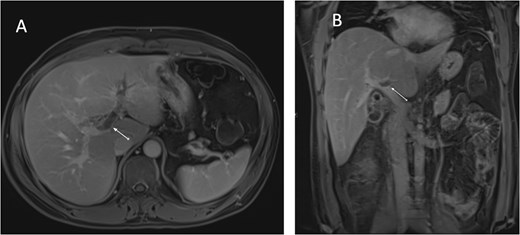

An ultrasound of the abdomen showed an impacted stone at the neck of the gallbladder with acute cholecystitis. The patient was admitted and started on IV antibiotics. He developed tachycardia reaching 110 bpm and had a high white blood cell count; therefore, the decision was made to proceed with a contrast-enhanced computed tomography (CT) scan, which showed evidence of acute cholecystitis and left PVT (Fig. 1). The medical team was consulted, and IV heparin without bolus was started. The gastroenterology team was consulted for his high bilirubin levels and advised for magnetic resonance cholangiopancreatography (MRCP), which was done the next day and confirmed the findings of left PVT (Fig. 2). MRCP also showed a micro perforation of the gallbladder and no biliary obstruction or stones (Fig. 3).

MRCP T1-weighted images: (A) axial cut; (B) coronal cut. Arrow indicates left portal vein thrombosis.